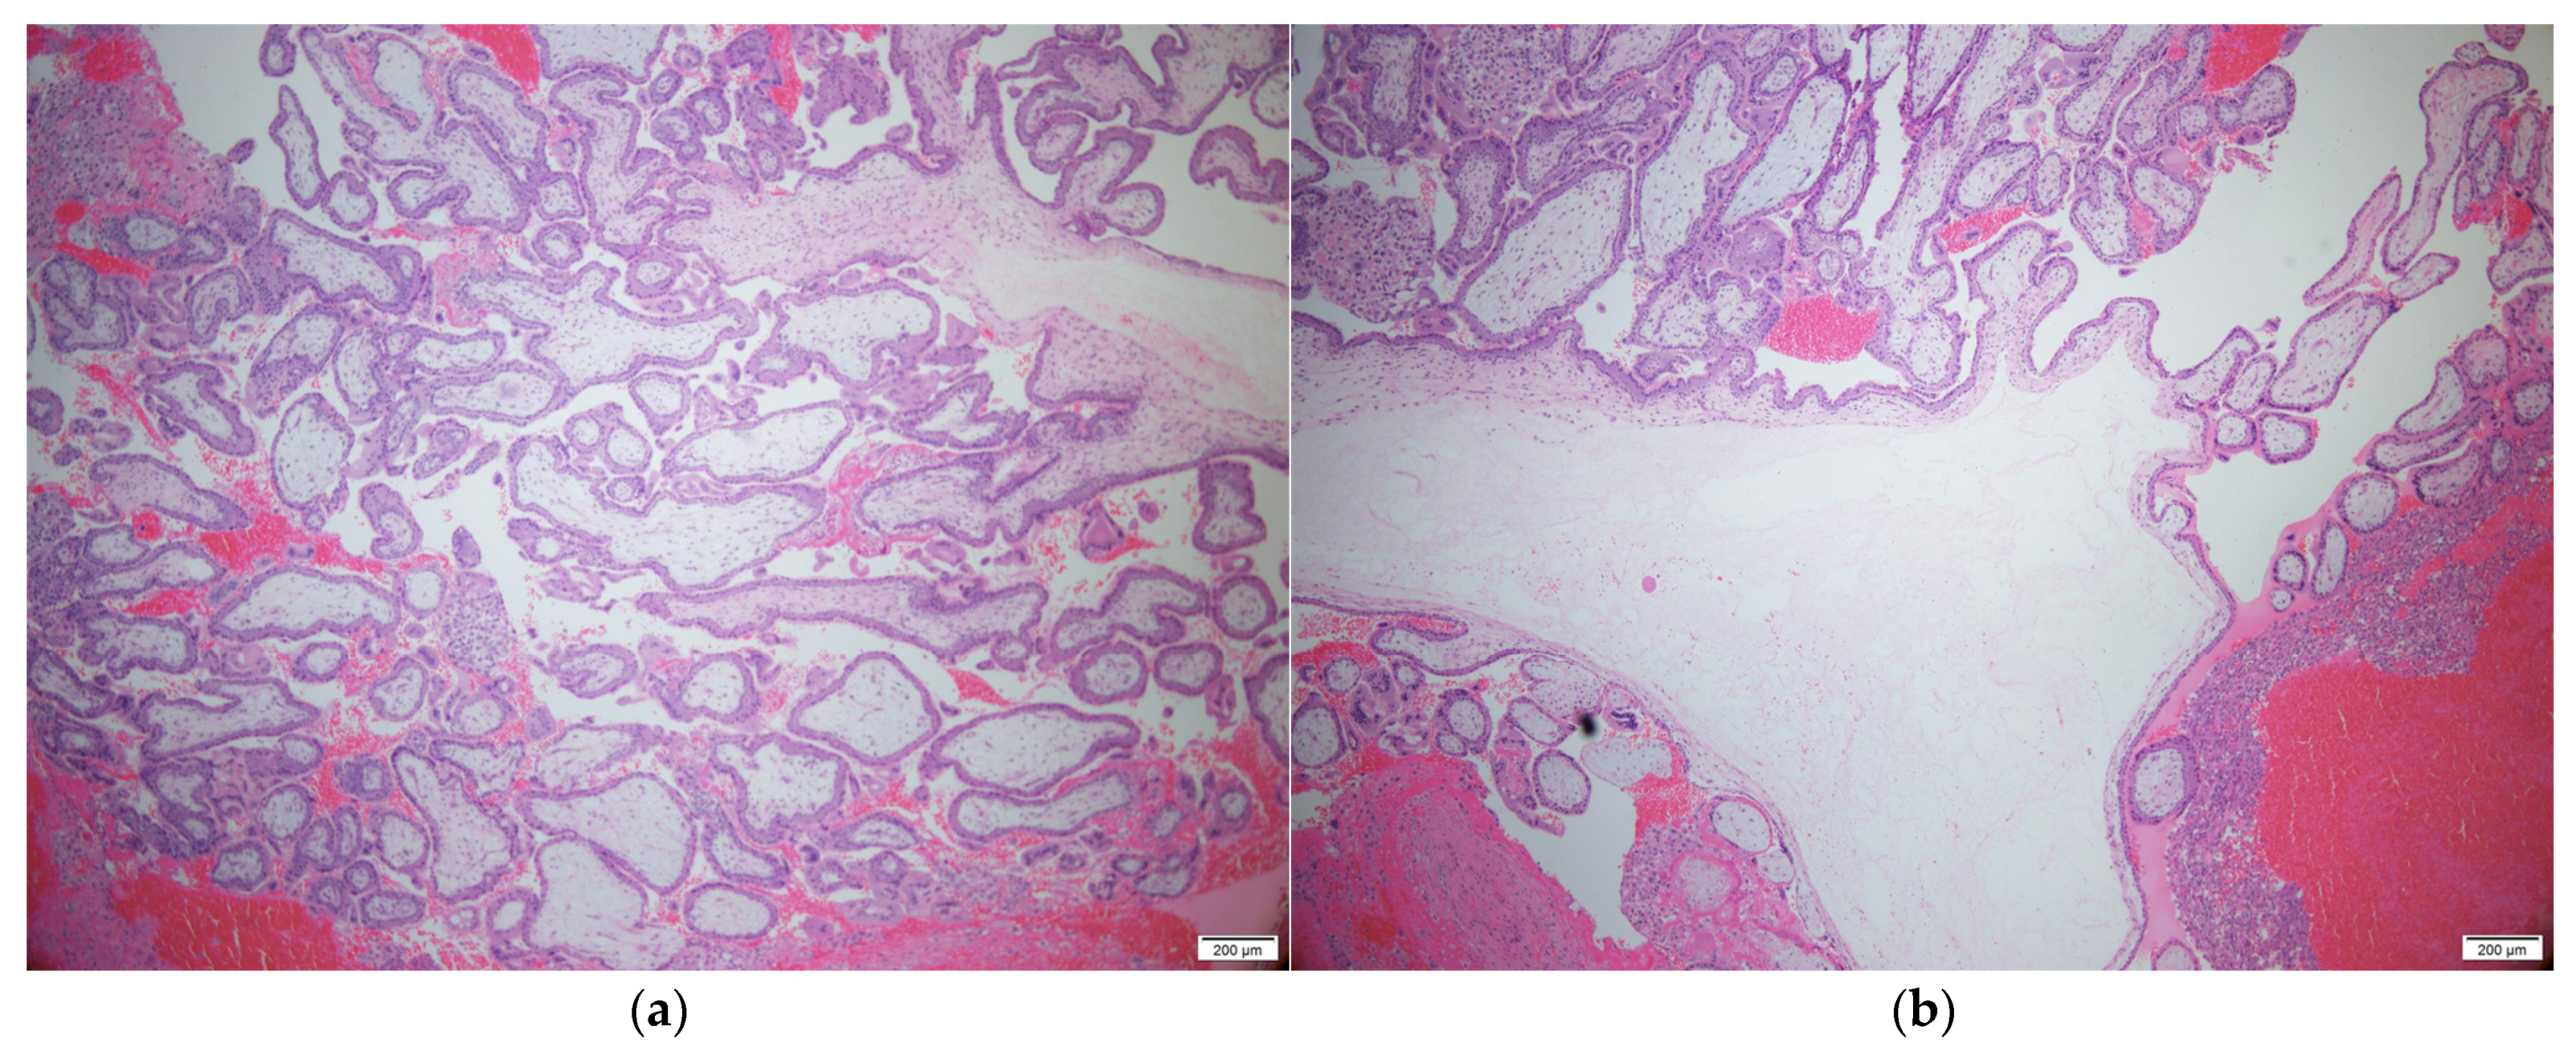

Figure 3. Histopathologic findings: Multiple chorionic villi in the periphery (a) and center (b) of the diaphragmatic ectopic disc are noted on H&E staining. (×50). Scale bar: 200µm.

A 34-year-old woman (gravida 3, para 3) with three spontaneous vaginal deliveries was transferred to the Ulsan University Hospital from a local clinic due to severe abdominal pain accompanied by right flank pain. The patient had been previously healthy and had no specific medical or surgical history. She had an irregular menstruation cycle, and her last menstruation occurred five weeks and six days previously. The initial vital signs at the emergency room were stable; systolic and diastolic blood pressure were 114 mmHg and 68 mmHg, respectively. The initial pulse rate was 71 beats per minute. Whole abdominal tenderness with muscle guarding was noted on physical examination. Blood tests showed a low hemoglobin level (10.7 g/dL). A urinary pregnancy test was positive, and the serum β-HCG level was 7377.0 mIU/mL. Gynecological sonography found no evidence of an intrauterine pregnancy, except for normal bilateral adnexa with free fluid collection, suggestive of hemoperitoneum. After eight hours, the follow up blood test showed a lower hemoglobin level (8.6 g/dL). Two packs of packed red blood cells were transfused. We suspected a ruptured ectopic pregnancy through elevated serum β-HCG, but the ectopic mass could not be identified on pelvic ultrasound. Thus, we planned abdominopelvic computed tomography (APCT) to determine the cause of the right frank pain. Approximately 2 cm hypervascular mass in the subphrenic region, with a moderate amount of hemoperitoneum, was revealed (Figure 1), which was thought to be the cause of the bleeding. Because of suspicions of a diaphragmatic ectopic pregnancy or other ruptured unknown hepatic mass, she was admitted for emergency surgery. Diagnostic laparoscopic surgery was performed in collaboration with a hepatobiliary surgeon and an obstetrician-gynecologist. On laparoscopy, about 400 mL of blood and clots were aspirated from the pelvic cavity, but both adnexa appeared normal. Approximately 20 × 10 cm tissue, suspected to be the placenta with a hematoma, had covered the diaphragm. After the removal of the placenta-like tissues, we found a 2 cm hypervascular mass attached to the diaphragm (Figure 2). The mass was completely resected from the diaphragm and sent for histological examination. After the surgical mass removal, the patient was discharged without any postoperative complications, and the serum β-HCG level normalized within a month. The final pathologic diagnosis indicated that the mass was a product of conception, consistent with an ectopic pregnancy (Figure 3).